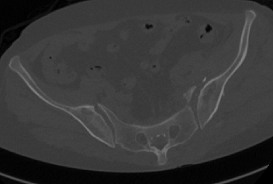

术前CT和术后CT比较

整个手术1小时内完成,通过术后CT影像证实3D打印导航模板引导骶髂螺钉置入安全、准确、创伤较小,手术时间短,患者也很快得到了较好的恢复。

近日,市四医院骨一科收治了一位特殊患者,该患者因车祸伤致骨盆多处骨折,经CT检查后,发现该患者骨盆有大大小小的骨折达8-10处,左侧骶髂关节明显脱位,双侧耻骨骨折。